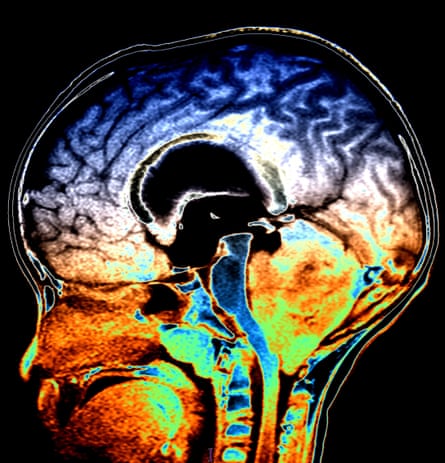

The race to reduce complications when treating children with cancer reached a much needed milestone in 2022. The most common aggressive brain tumour affecting children is medulloblastoma, which grows in the cerebellum at the back of the brain. Every year in the UK, around 50 children face this diagnosis. Ongoing research has established four subtypes of medulloblastoma, which can help doctors develop better treatment plans. Around 70% of children survive medulloblastoma for five years or more, but recent findings by Cancer Research UK scientists, led by Prof Steve Clifford at Newcastle University, are paving the way for even more honed treatments.

“The sequencing tools available to us now allow us to see, in much greater detail, the driving forces behind the different types of medulloblastoma at the single-cell level,” says Clifford. Among their discoveries is that tumours in the subtypes with the highest survival rates contain genetically identical cancer cells, whereas the harder to treat tumour types have three or four different types of cancer cells. This gives them a better chance of evading treatment. The team also discovered a way to identify subtypes more easily, which could avoid the need to take multiple biopsies.

An MRI scan showing medulloblastoma, the most common aggressive brain tumour affecting children. Photograph: Science Photo Library

“We are now at the stage where we can clearly see what changes cause medulloblastoma to emerge in the first place, and the paths it can go down that determine how aggressive it is likely to be,” says Clifford. These crucial findings could lead to more effective treatments.